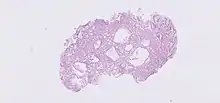

H&E stain of fundic gland polyp showing shortening of the gastric pits with cystic dilatation

The polyps on endoscopy are usually tiny, numerous and sessile,[3] and usually scattered throughout the fundus of the stomach, where parietal cells are more numerous. They have the same colour as the gastric mucosa, and never have a stalk.[4] When the polyps are biopsied, the pathology typically shows shortened gastric pits, and both superficial and deep cystic lesions in the fundic glands, lined by all three types of cells of acid-producing mucosa: mucous, parietal and chief cells. As sometimes parietal cell hyperplasia may develop deep dilations of gland,[5] one should be really strict in the diagnosis of FGPs (i.e. the presence of deep and superficial dilations). Infrequently, the two lesions may coexist.[3] Foci of dysplasia can sometimes be seen.[4]